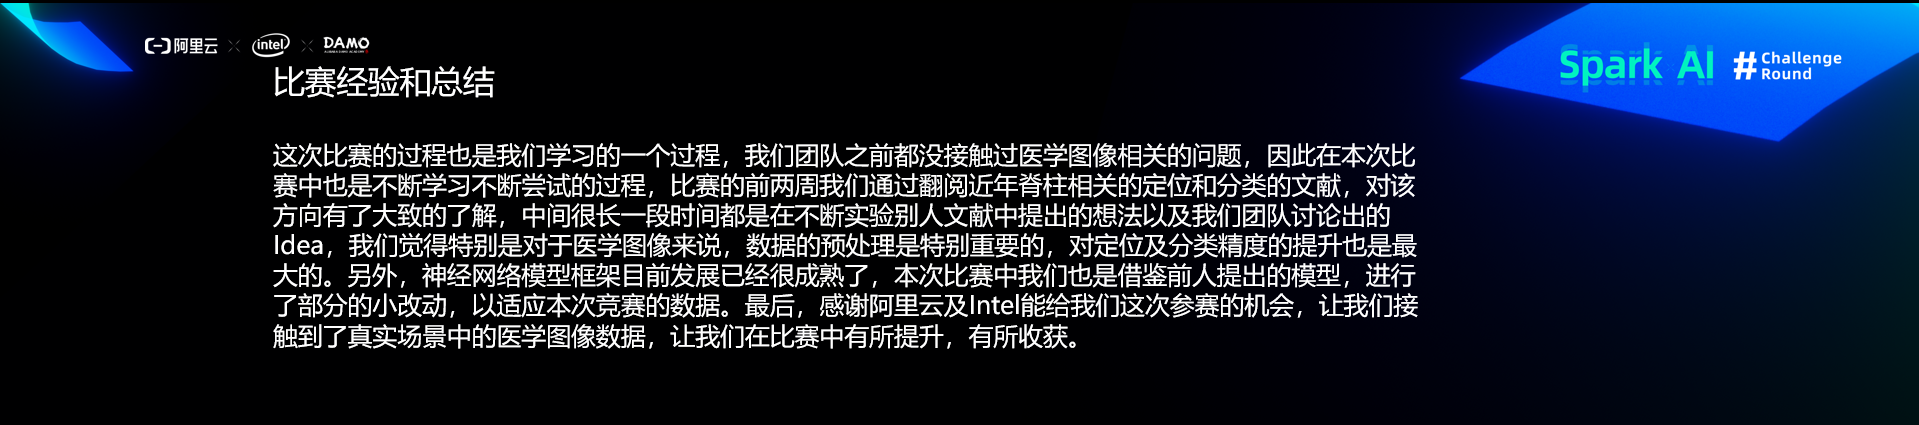

比赛经验和总结